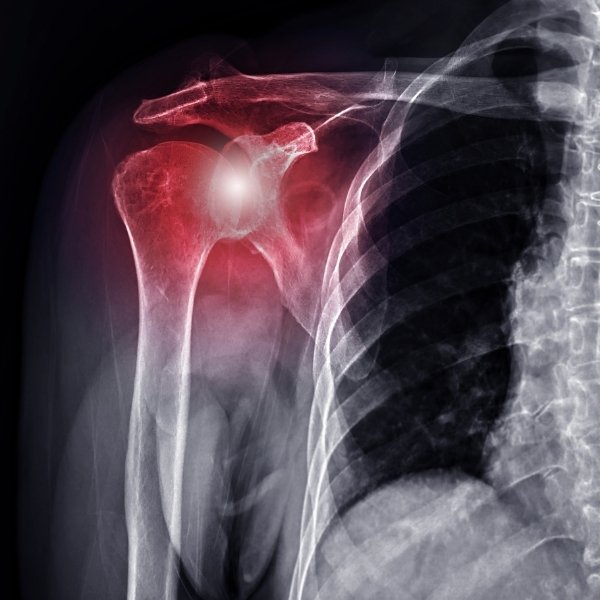

Luxación de Hombro

Tratamiento de Luxación de Hombro en Santa Cruz

El hombro es la articulación con mayor movilidad del cuerpo, pero esa libertad tiene un precio: es la que más se sale de su lugar (luxación). Una luxación anterior ocurre cuando la cabeza del húmero se desplaza hacia adelante y fuera del orificio glenoideo, rompiendo ligamentos y el labrum (lesión de Bankart) e incluso dañando el hueso (lesión de Hill-Sachs).